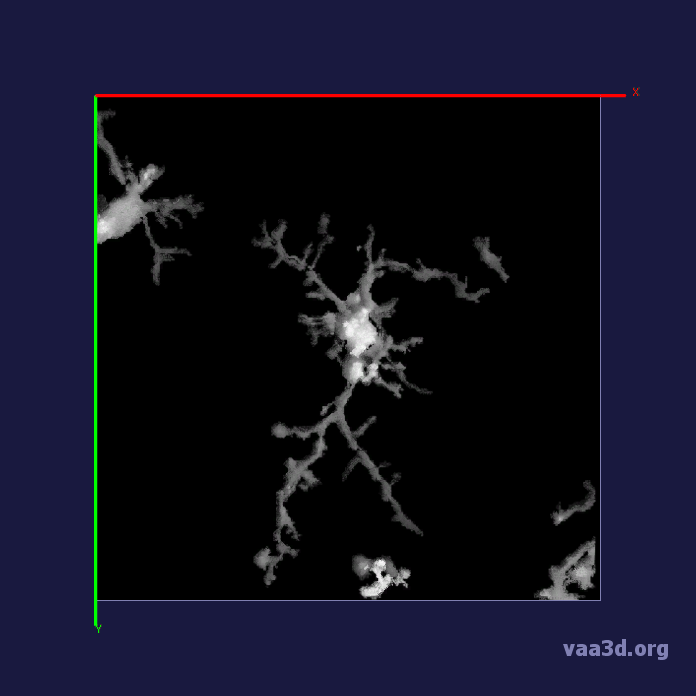

In our experiments, we compare the coupled TuFF-BFF microglia segmentation results with those given by L2S [21] and the Chan-Vese segmentation method [22]. The groundtruth in 3D was attained by manually tracing the object slice by slice from the z-stack. It must be noted that this was done by eye and could have some error. Figure 2 shows the visual comparison of the segmentation results for our dataset. Our result shown on the third column captures both the soma and processes. Figure 3 shows the Dice coefficient comparison of each segmentation method to the ground truth. Since the soma is much larger than the fine processes in the microglia, the processes have less volumetric impact on the similarity score. As explained in Section 1, segmenting the processes is important for quantifying the extension from the soma and its volume of surveillance. We use the Dice coefficient to quantitatively compare the ramification by taking the convex hull of the resulting segmentation. The Dice coefficient is a similarity measure that is computed using with where is the ground truth and is the compared image.

From Figure 4, the average Dice score for coupled TuFF-BFF was 0.77, compared to 0.53 for L2S [21] and .58 for Chan-Vese [22]. It must be noted that L2S required manual user initialization for each 2D image in the stack. While the Chan-Vese method has automatic seed selection, our coupled TuFF/BFF method was the only method that was a true 3D segmentation algorithm. L2S could not consistently capture the entire processes due to the intensity inhomogeneity throughout the object and background noise. The Chan-Vese segmentation could capture the extensions of the processes but did not work well with noise and attained false positives in the reconstruction. Since our method uses the tubular and blob information of the object to separate foreground and background, the segmentation only evolved within the object boundaries.

From the segmentation of microglia from 3D multiphoton images, we attained quantification of the ramification of the microglia processes using the index provided by Madry et al. The ramification index in Table 1 quantifies the extension of the processes from the soma. The ramification index of 1 is the soma with no ramification and a larger index denotes greater ramification. We compare the ramification index attained from the segmentation result from each method with that attained from the ground truth. The mean absolute error for coupled TuFF-BFF was 1.49 compared with 3.92 and 3.78 for L2S [21] and Chan-Vese [22], respectively.